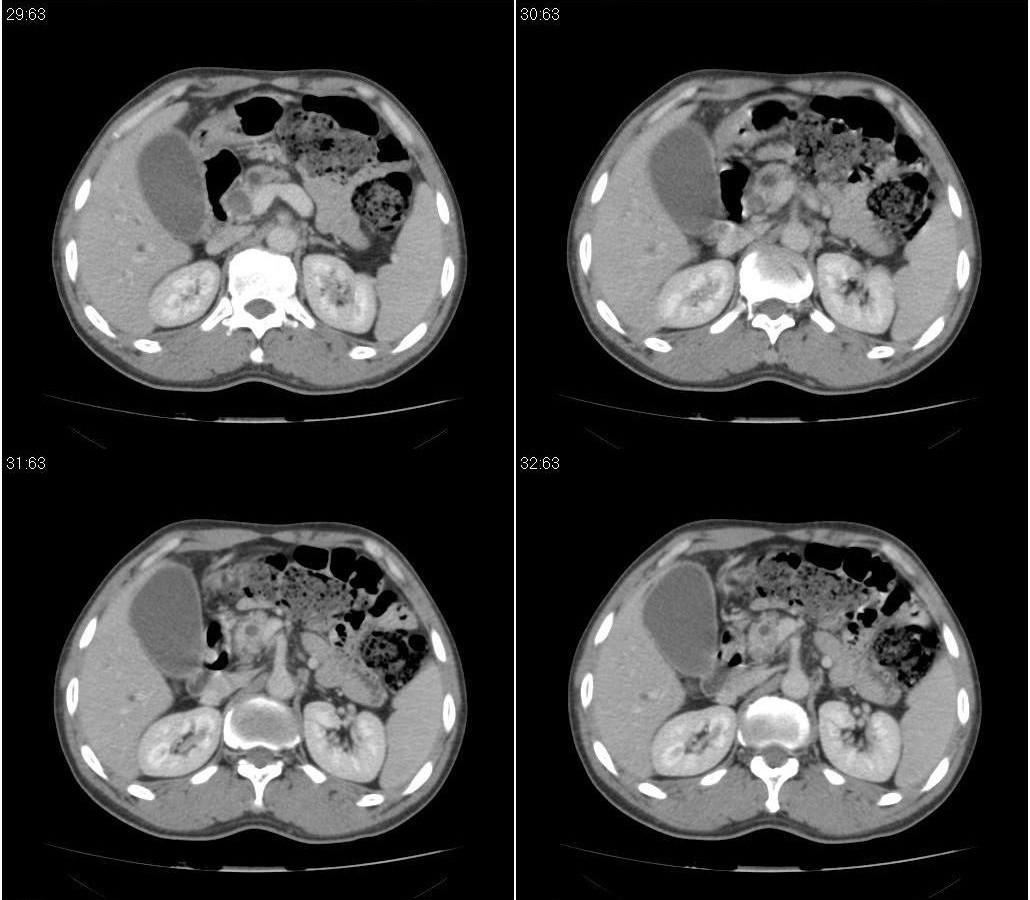

标题: CT21384:男性,50岁。发现无痛性黄疸十余天,B朝提示肝胆管 [打印本页]

标题: CT21384:男性,50岁。发现无痛性黄疸十余天,B朝提示肝胆管

1.考虑:壶腹占位病变(癌?)。

2.胆系低位梗阻:肝内外胆管扩张,胆囊增大,胰管扩张。

胰头癌伴低位胆道梗阻。

胆系低位梗阻(肝内外胆管扩张,胆囊增大,胰管扩张);考虑胰头癌或壶腹癌所致。

胰头强化欠均匀,胆胰管扩张。考虑胰头癌可能性大。

胆系低位梗阻(肝内外胆管扩张,胆囊增大,胰管扩张,钩突似有占位);考虑胰头癌